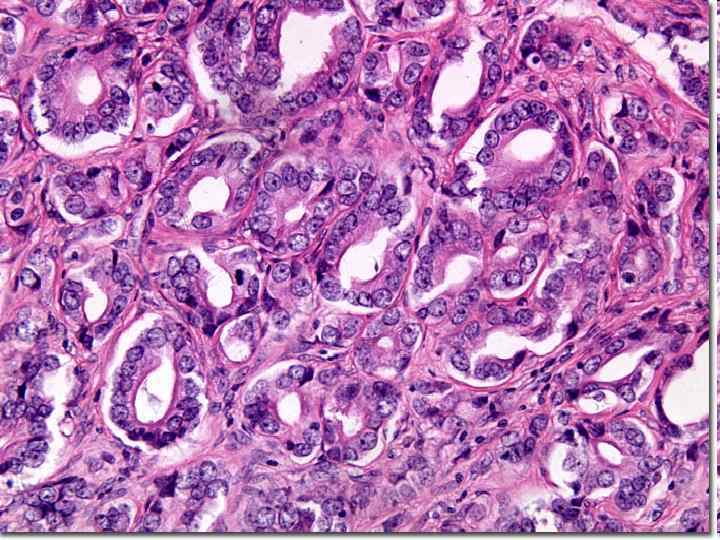

Опухоли эндометрия n Полипоз (доброкачественное, предраковое заболевание) n РАК - рост экзо- и эндофитный Гистологическиаденокарциномы и недифференцированные раки n